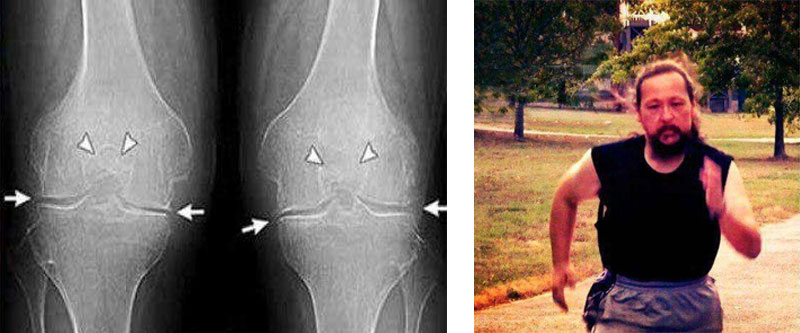

35-η

μέρα:έκανα εξετάσεις και ακτινογραφία του ώμου και του αγκώνα. Δεν υπάρχουν ίχνη αρθρώσεων! Ο

χόνδρος στις αρθρώσεις είναι σαν ενός νεαρού 30 ετών. Ο γιατρός είπε ότι στην προηγούμενη ακτινογραφία

υπήρχε πιθανότατα ένα ελάττωμα, οπότε η διάγνωση της οστεοαρθρίτιδας ήταν εσφαλμένη.

διαφορά:

πόδι μου. Ο πατέρας μου μου έφερε από κάπου το και Curcumactiv Δόξα το Θεό! Δείτε την διαφορά: